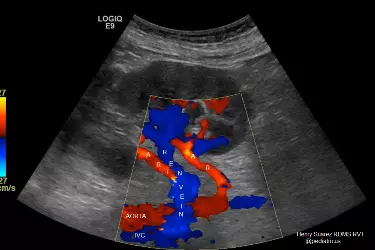

Patients suffering from High Blood Pressure for a long time may suffer damage to the kidneys. Diabetic patients with uncontrolled sugar also have a tendency of narrowing of the blood vessels. Such patients would have atherosclerosis in almost all the arteries of the body. Colour Doppler of the Renal Arteries is done to see the blood flow in the Renal Arteries. Any kind of blockage in these arteries reduces the flow of blood to the kidneys and result in kidney damage. Any kind of blockage in the Renal Arteries is called Renal Artery Stenosis. If this condition is found in Colour Doppler Study then treatment can be started at the right time in order to prevent damage to the kidneys. If this condition is not diagnosed timely then the patient may end up having Renal Failure which would require regular dialysis or Kidney Transplant.

If there is stenosis in the renal arteries then the blood flow in the renal arteries would be greater than 180 cm/sec. If the blood flow in the renal arteries is less than 180 cm/sec then it signifies normal renal artery. Any kind of stenosis of blockage in the arteries would reduce the size of the artery through which blood can flow and this increases the speed of the blood flow in the artery. For fatty patients it is difficult to do Renal Colour Doppler on normal ultrasound machines. We have installed High Resolution Colour Doppler machines which can do the doppler study for fatty patients also. All the patients who are suffering from hypertension or diabetes should get colour doppler of the kidneys, carotid doppler and echocardiography to rule out any blockages in these important blood vessels.